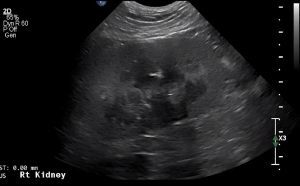

SIMON Ultrasound Database

This ultrasound database is a free resource for students and doctors!

Our collection includes videos of dogs, cats, horses, cows, humans, and many other species!